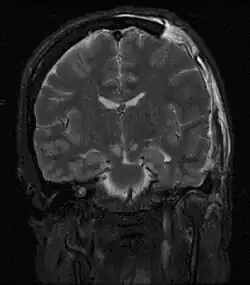

| MRI showing injury due to brain herniation | |